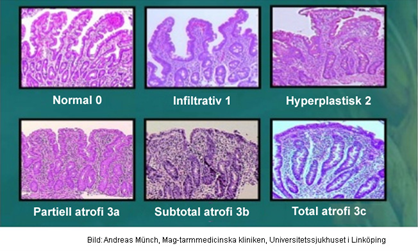

Bedöm biopsin

- Kolonslemhinna med kroniskt och akut inflammatoriskt infiltrat i lamina propria och intraepitelialt. Granulom påvisas. Kryptarkitekturen är oregelbunden.

- Morbus Crohn – granulom ganska specifikt

Hur vill då gå vidare i utredningen och varför?

- Esofagogastroduodenoskopi med biopsitagning från duodenum

- Värdera om celiakin är remission

Vad kallas systemet?

Marsh

Vad visar kolonbiopsin?

- Förtjockat subepitelialt kollagenband och ökad halt inflammatoriska celler i lamina propria och bland enterocyterna. Förlust av bägarceller

- Mikroskopisk kolit/kollagen kolit

Vad ser du på den uppförstorade biopsin?

- Kollagen som omger kapillärer och innehåller inflammatoriska celler. Ytepitelet är degenerativt förändrat och uppvisar karaktäristisk avlossning

- Förlust av bägarceller

- Mikroskopisk kolit/kollagen kolit

Vad ser du på den uppförstorade biopsin?

- Visualisering av förtjockat kollagenband och att dess nedre del är oregelbundet

- Mikroskopisk kolit/kollagen kolit